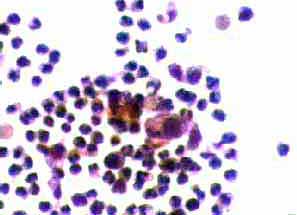

Aσθενής 45 ετών, με γνωστή παρουσία πολλαπλών κύστεων και στους δύο μαστούς εδώ και πολλά χρόνια.. Επώδυνη κύστη διαμέτρου 4 εκ. στον αριστερό μαστό. Κάτω από υπερηχογραφικό έλεγχο παρακέντηση και αφαίρεση περίπου 20 κ. εκ. κιτρινωπού υγρού.

Ομάδες ομοιόμορφων  κυττάρων τοιχώματος κύστης μαστού. Πολυμορφοπύρηνα..

Άμεση χρώση στεγνών παρασκευασμάτων, χωρίς μονιμοποίηση, κατά Papanicolaou και με  bleu de methylen.